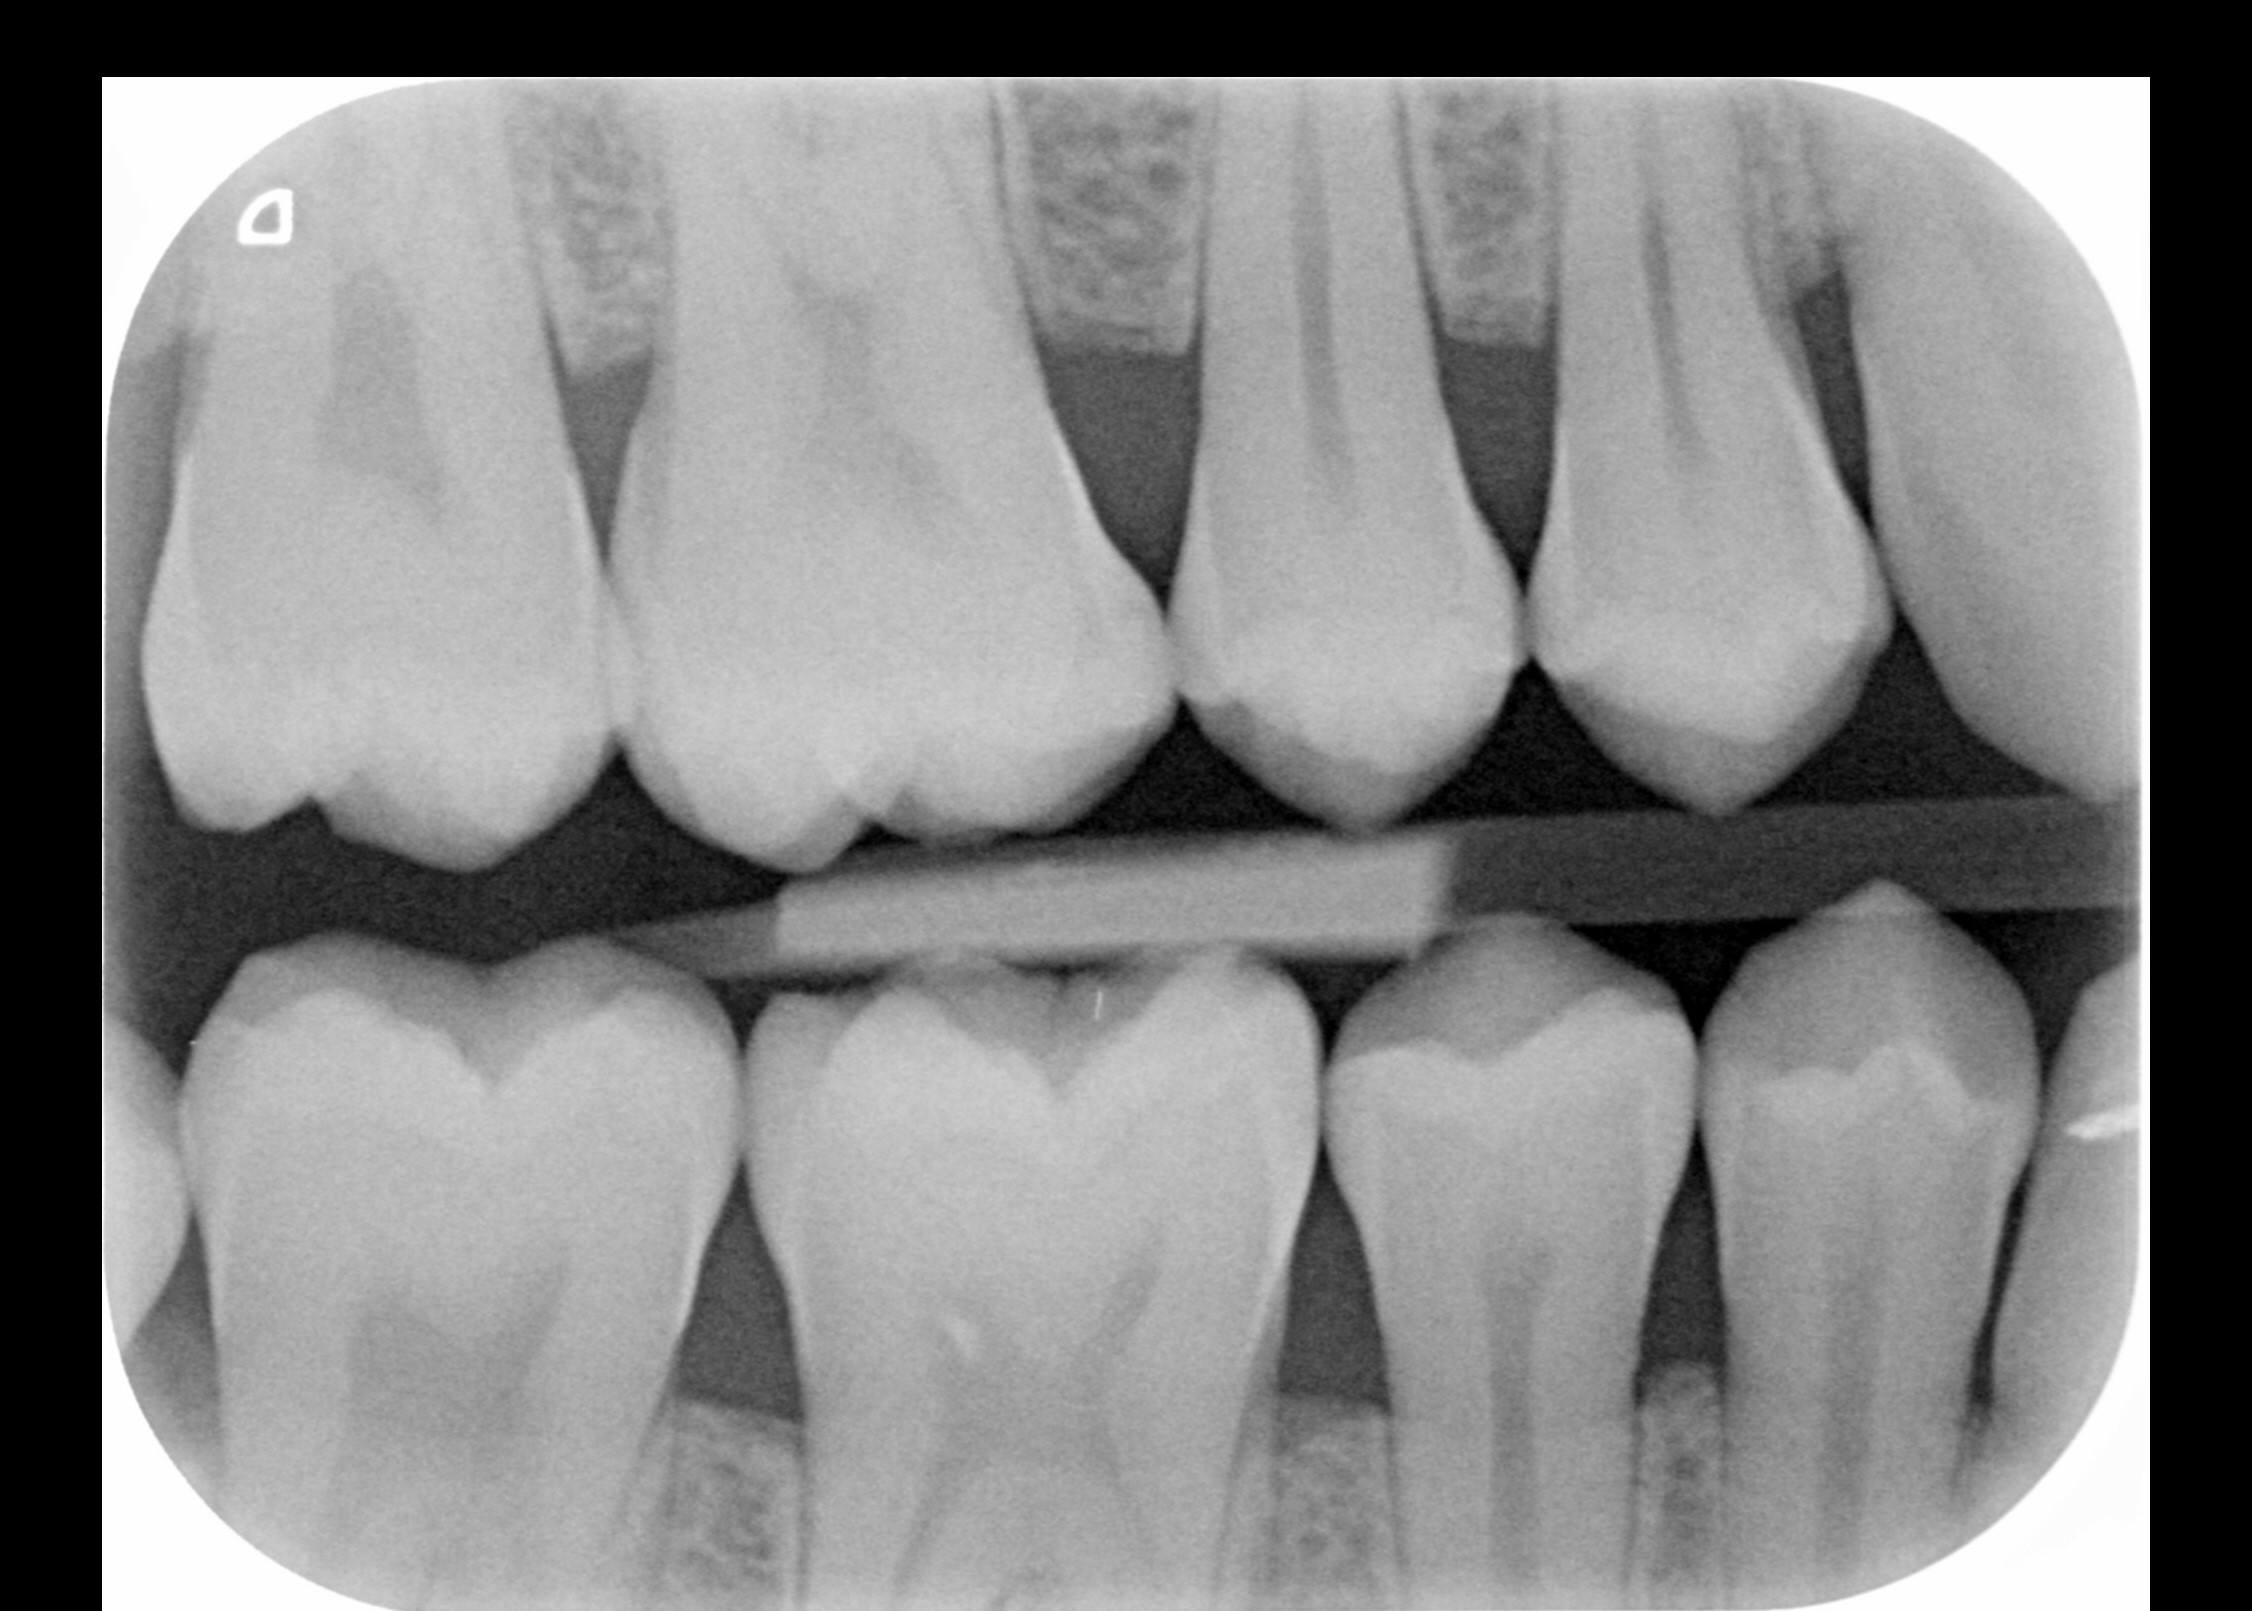

Heb al circa een week last van pericoronitis (wel vaker gehad). Deze keer duurt de genezing wat langer. Pijn is helemaal weg, maar het tandvlees daar is nog zacht en niet strak tegen de verstandskies. Foto 1 is hoe het nu is, zacht tandvlees, en foto 2 toen het gezond was waarbij het tandvlees strak is. Wanneer zal de zachtheid weggaan? Ik spoel al dagelijks met zoutwater. Ben ook van plan om in 2026 mijn verstandskiezen te verwijderen. Foto 3 en 4 zijn foto's van mijn verstandskiezen, heb alle 4 al meer dan 12 jaar niet laten trekken, maar denk dat ik het beter kan doen? Werd wel vaak gezegd tegen me dat het slim is om ze te laten trekken, maar ik ben altijd bang van zulke behandelingen.

Ik zou ze laten verwijderen... Waarom wachten op weer een irritatie. Het ziet er niet verontrustend uit...goed schoon houden. Let ook op uw drink en eet gewoonten... Flink slitage. Of ander oorzaak??. Bot trekt ook iets omlaag..Ragers gebruiken bij ieder poets beurt....hoop dat u niet rookt.